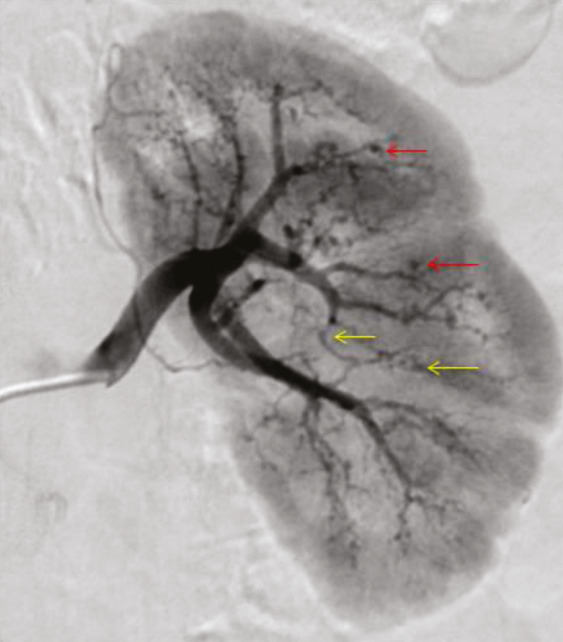

Les atteintes digestives et rénales sont vasculaires, en lien avec des sténoses des moyens vaisseaux, responsables de phénomènes ischémiques et/ou de microanévrismes (fig. 4).6 Leur diagnostic se confirme à l’imagerie, notamment par une angiotomodensitométrie (TDM). L’artériographie, examen de référence, peut s’avérer nécessaire, à visée diagnostique en cas de négativité de la TDM,2 mais surtout à visée thérapeutique, permettant une artério-embolisation en cas d’hémorragie grave.

L’atteinte rénale se manifeste soit par une hypertension artérielle isolée, parfois sévère, soit par une authentique néphropathie vasculaire (insuffisance rénale aiguë, protéinurie tubulaire +/- hématurie microscopique, stigmates biologiques de microangiopathie thrombotique).16 Elle est en lien avec des sténoses, pouvant aussi entraîner des infarctus rénaux. Les microanévrismes des artères rénales et de leurs branches peuvent être responsables d’hématomes sous-capsulaires ou rétropéritonéaux.17 Si l’insuffisance rénale ne se voit que dans 12 % des PAN,5,6 cette néphropathie vasculaire, non glomérulaire, représente un enjeu diagnostique majeur. Contrairement aux autres vascularites, notamment celles ­associées aux anticorps anticytoplasme des polynucléaires neutrophiles (antineutrophil cyto­plasmic antibodies [ANCA]), la biopsie rénale ne doit pas être réalisée avant d’avoir exclu les microanévrismes en artériographie, au ris­que de complications hémorragiques.16,18

Imagerie artérielle non invasive en première intention

L’imagerie artérielle peut suffire à poser le diagnostic, en cas de suspicion clinique et de présence d’anévrismes sacciformes ou fusiformes, de sténoses des artères de moyen calibre, notamment rénales, hépatiques ou digestives.2,4 En première intention, une imagerie non invasive telle que l’angio-TDM ou l’angio-­IRM (en cas de contre-indication aux produits de contraste iodés) est recommandée mais nécessite un regard exercé de la part du radiologue. L’artériographie reste l’examen de référence en cas de doute diagnostique, mais n’est réalisée qu’en deuxième intention, compte tenu d’éventuelles complications, à type d’hématome, de faux anévrismes au point de ponction ou de néphropathie aux produits de contraste.2 Elle peut aussi jouer un rôle thérapeutique, en cas de saignement sévère, permettant de réaliser une embolisation.